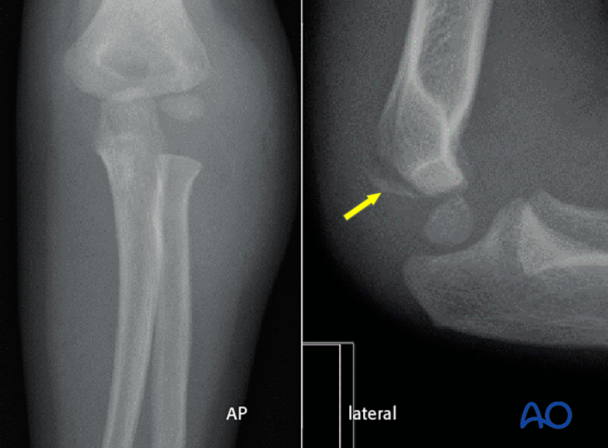

X线评估必须包含三个位置:肘关节正位、侧位和内斜位,缺一不可。内斜位能最大程度显示骨折线位置和移位,揭示其他体位遗漏的细节。

图6:A 左肘正位X线片,轻度移位,内外侧间隙宽度相同。B 同一肘部的内斜位X线片显示移位较大。

图7: 侧位片需关注Thurstan Holland征(后侧三角形骨片),这是诊断的有力证据。

CT不但可以更快地获取图像,而且可以更准确地判断骨折移位情况,患儿不需要镇静,是评估儿童外侧髁骨折的有效工具。

图8: X线上骨折移位情况不清晰;但CT检查能精准判断骨折块移位情况;